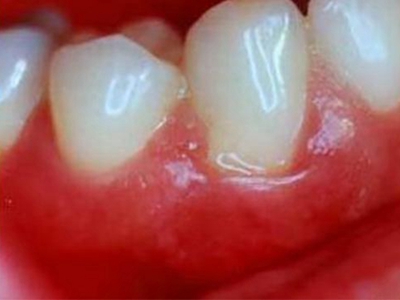

牙龈炎是发生于牙龈组织的炎症,患者可出现牙龈出血伴肿胀、发红、正常形态改变和偶尔不适等症状。本病主要由口腔卫生状况差导致,包括口腔不洁、牙菌斑等,诊断依据临床检查,治疗包括专业牙齿清洁和加强家庭口腔卫生。

牙龈炎可先引起牙齿与牙龈之间的沟(龈沟)加深,然后牙龈充血,炎症围绕一个或多个牙齿,伴牙龈乳头肿胀和易出血。一般无痛,可自行消退,也可维持轻度炎症数年。